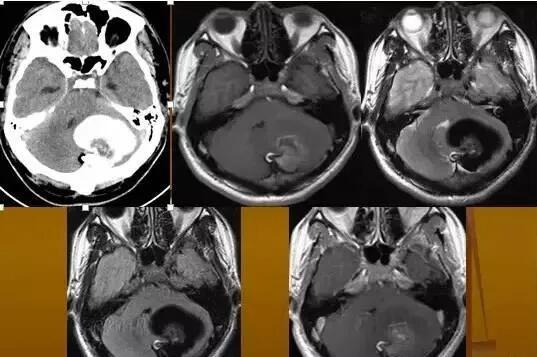

皮樣囊腫

CT表現(xiàn):平掃腫瘤呈球形低密度,邊緣銳利,CT值低于腦脊液,但高于脂肪密度,看不到囊壁,無強(qiáng)化效應(yīng)。

MRI表現(xiàn):

皮樣囊腫呈囊狀,邊界清楚,在T1WI上呈高信號,T2WI亦為高信號,但信號強(qiáng)度較低。由于其內(nèi)含有毛發(fā)等不同成分,信號可不均勻,以T2WI為著。

脂肪抑制像可見高信號消失,增強(qiáng)掃描病灶無明顯強(qiáng)化,部分囊壁可見強(qiáng)化。皮樣囊腫破裂后,病灶與周圍組織分界欠清,蛛網(wǎng)膜下腔或腦室內(nèi)可見脂肪信號影,腦室內(nèi)脂液界面可見化學(xué)位移偽影。較小的皮樣囊腫破裂因其內(nèi)容物外溢而塌陷閉塞。